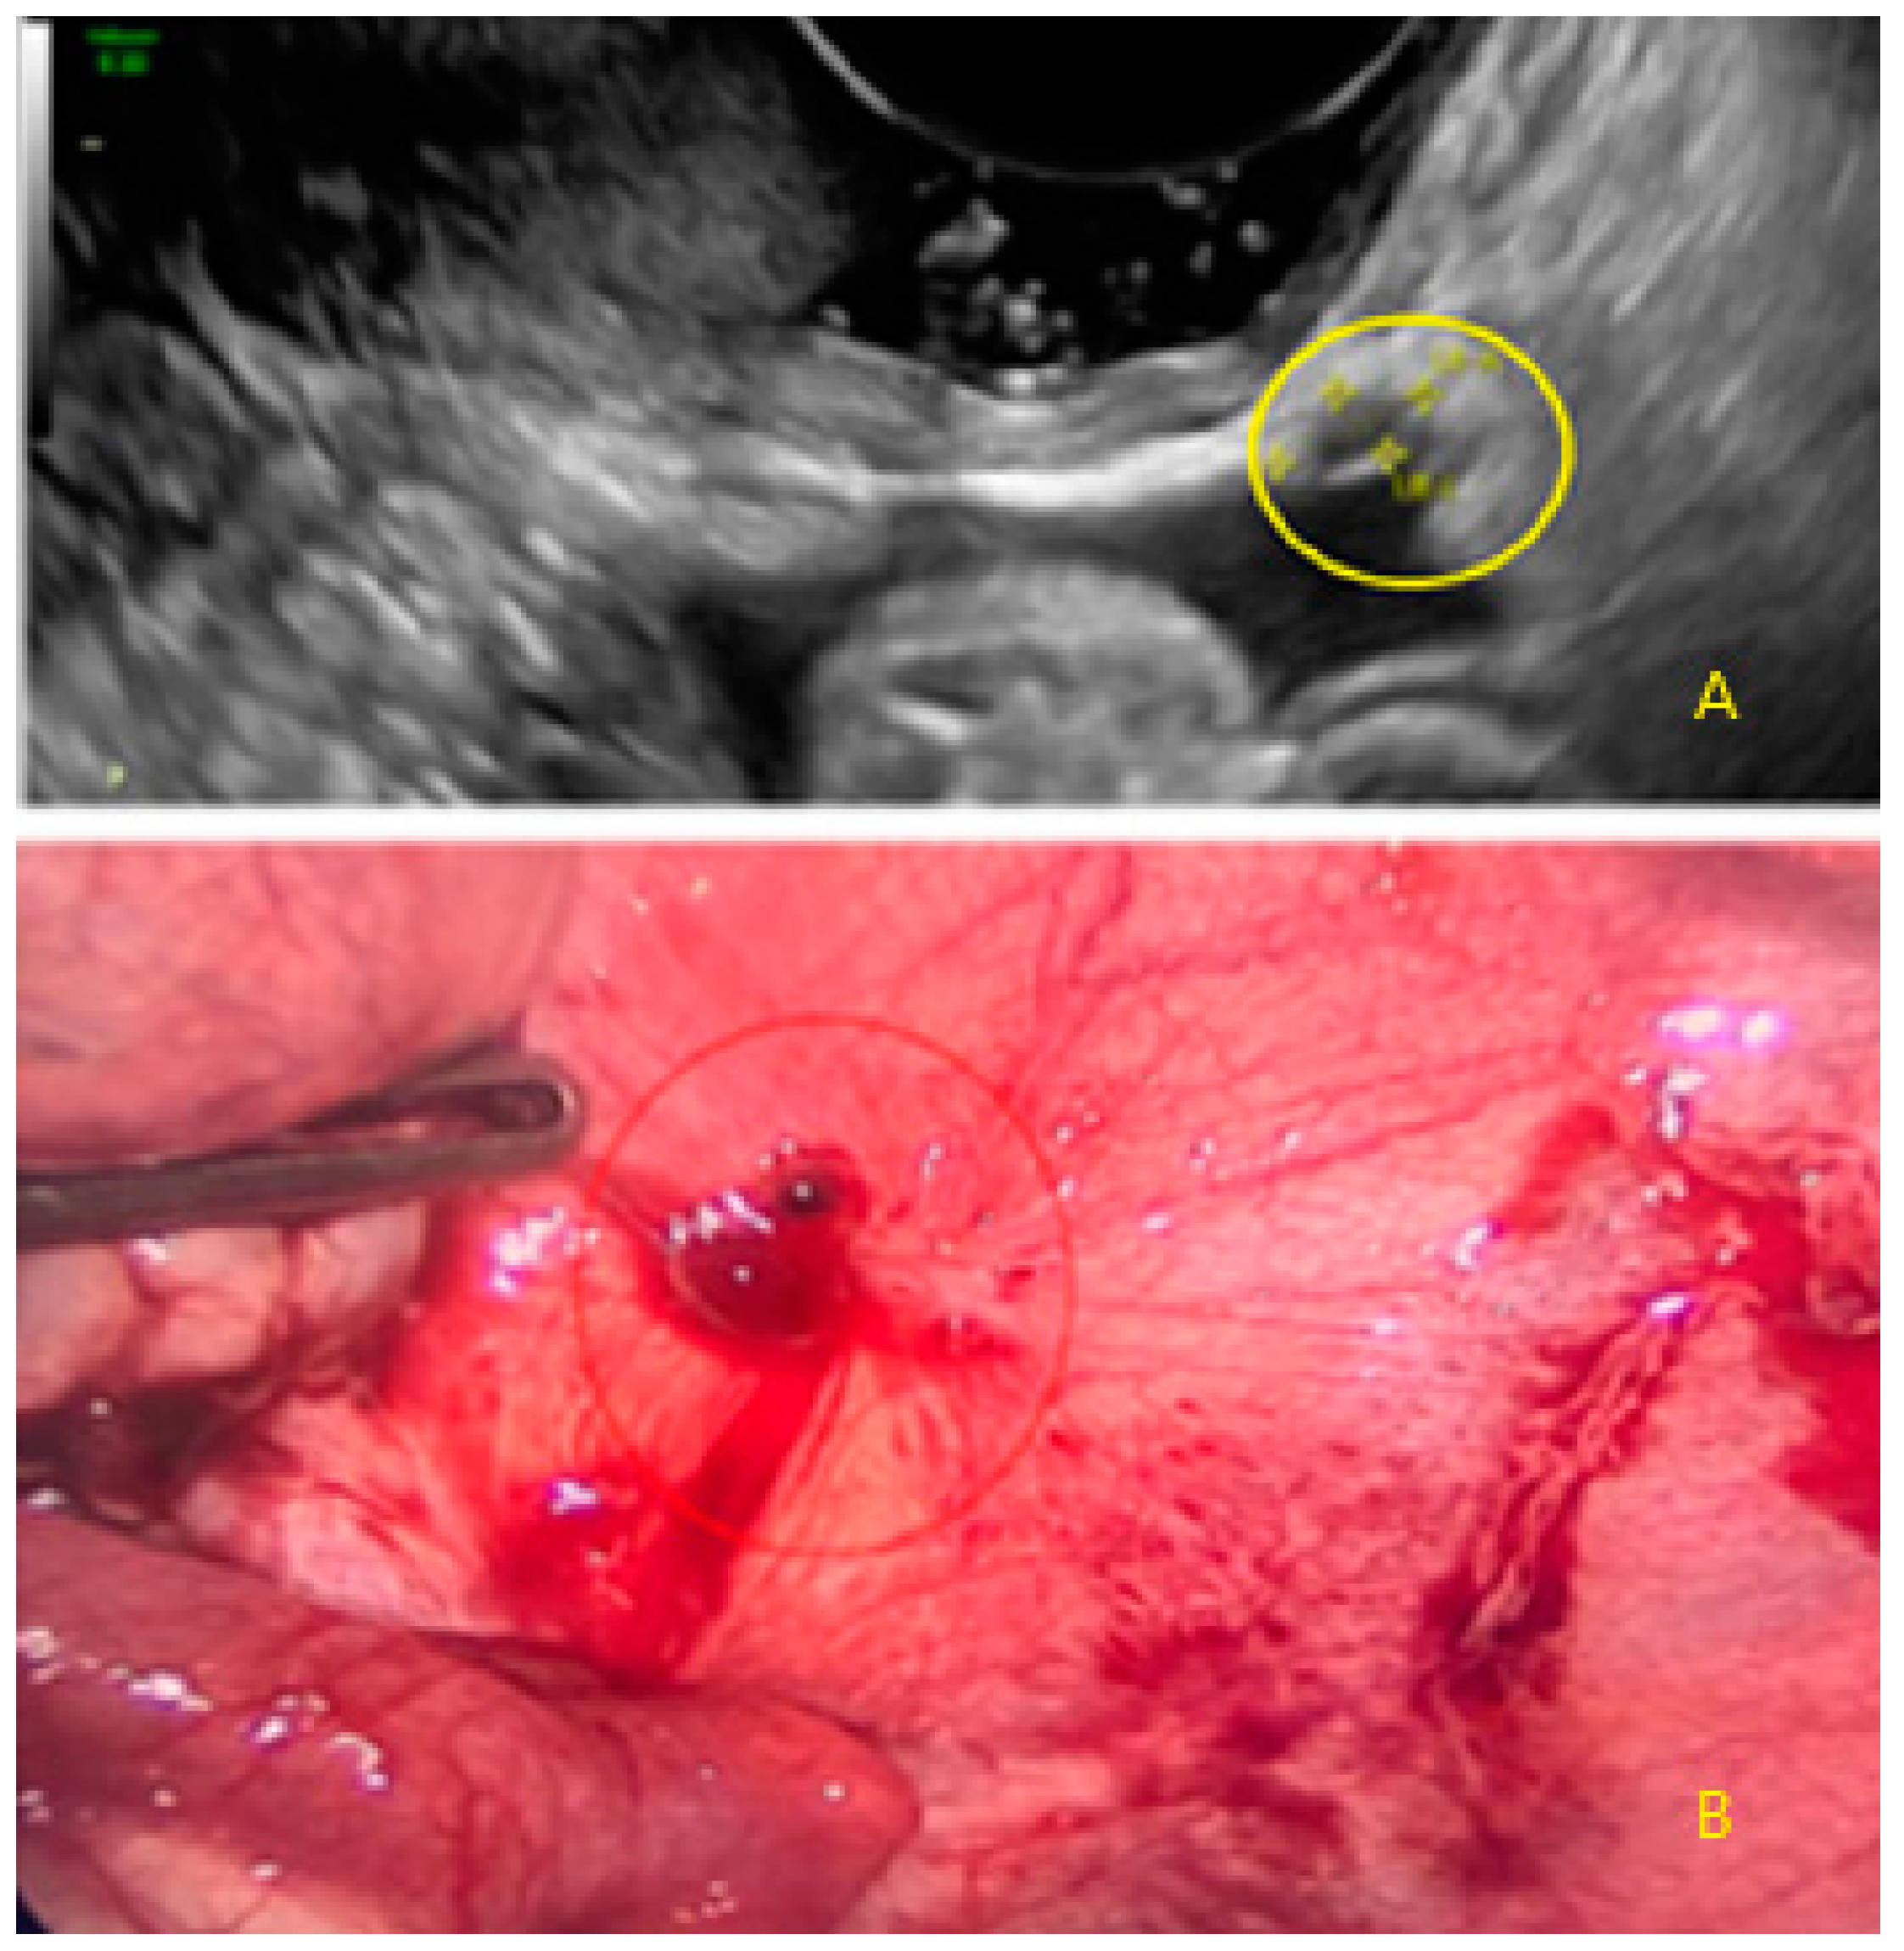

- The presence of hypoechogenic associated tissue (hypoechoic areas surrounding a small cyst area; we called this a “hat”). This tissue does not protrude or invaginate the peritoneal surface.

- The lesion may be convex, protruding from the peritoneal surface into the peritoneal cavity (we called this “bulging”), or it may appear as a concave defect in the peritoneum (we called this a “pocket”).

- The presence of hyperechoic foci (we called this a “pearl”).